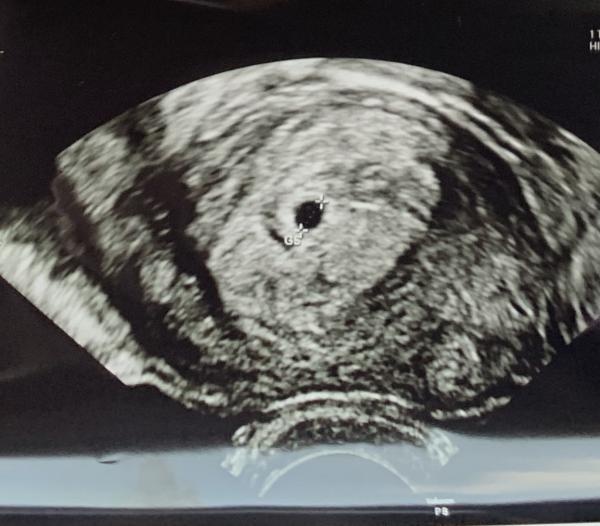

Såhär såg mitt ultraljud ut i vecka 5, en liten prick bara!

@corros @lizziep : tack så mycket!! Underbara lilla pricken